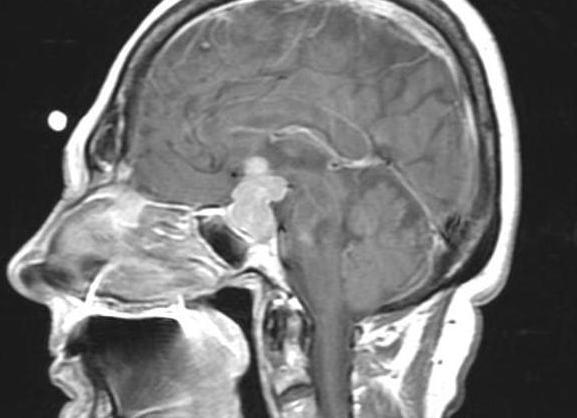

Магнитно-резонансная томография представляет собой новейшую методику диагностирования патологий. Ее используют для осмотра внутренних органов, систем и сосудов. МРТ нередко применяют при патологиях, связанных с ЛОР-органами, например, для обследования пазух носа. Обследование носовых пазух может производиться как при полноценном исследовании головы, так и отдельно. МРТ используют достаточно редко, это связано с тем, что более простые и доступные процедуры, как КТ и рентген носовых пазух, позволяют диагностировать заболевания носовых полостей достаточно точно. МРТ незаменима в сложных случаях, например, при наличии у пациента патологических процессов в области носоглотки, при осложненных клиновидных и решетчатых пазухах. Подробнее ...